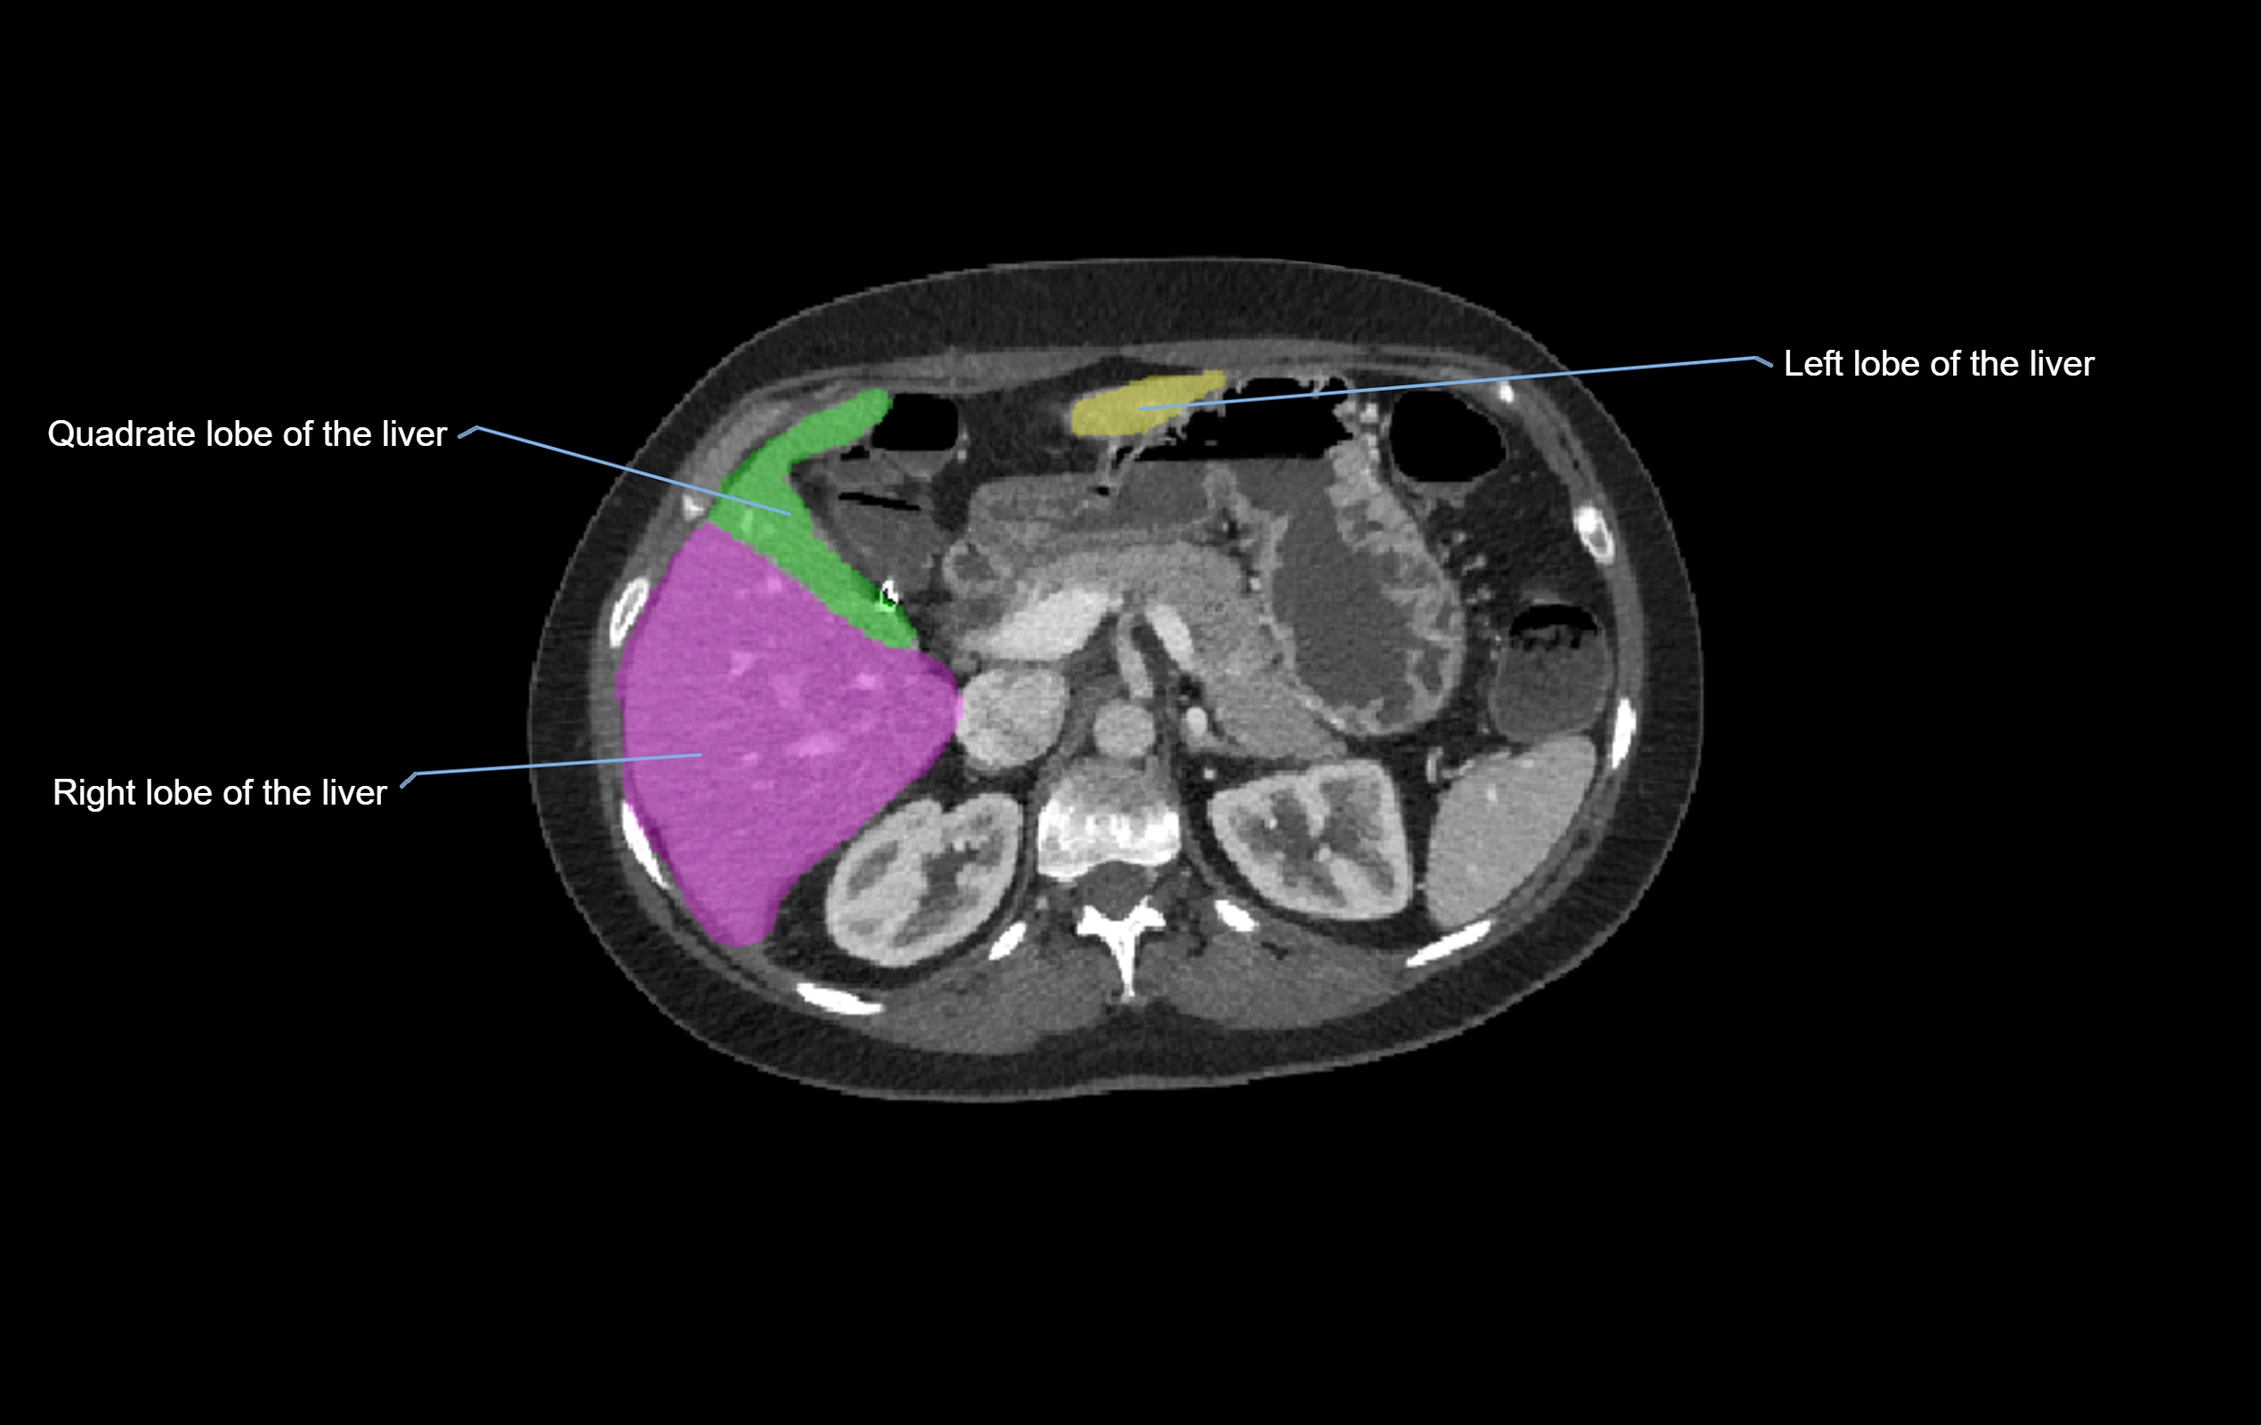

MRI image

image